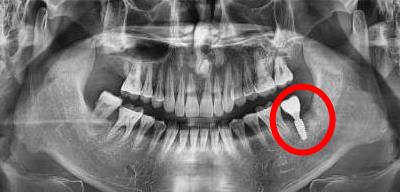

3、口腔全景片能看到種植牙嗎

可以的,種植牙等修複體(ti) 在口腔全景片上展現的通常是白色的,可以很清晰的看出來,比如下圖中就有1顆種植牙。